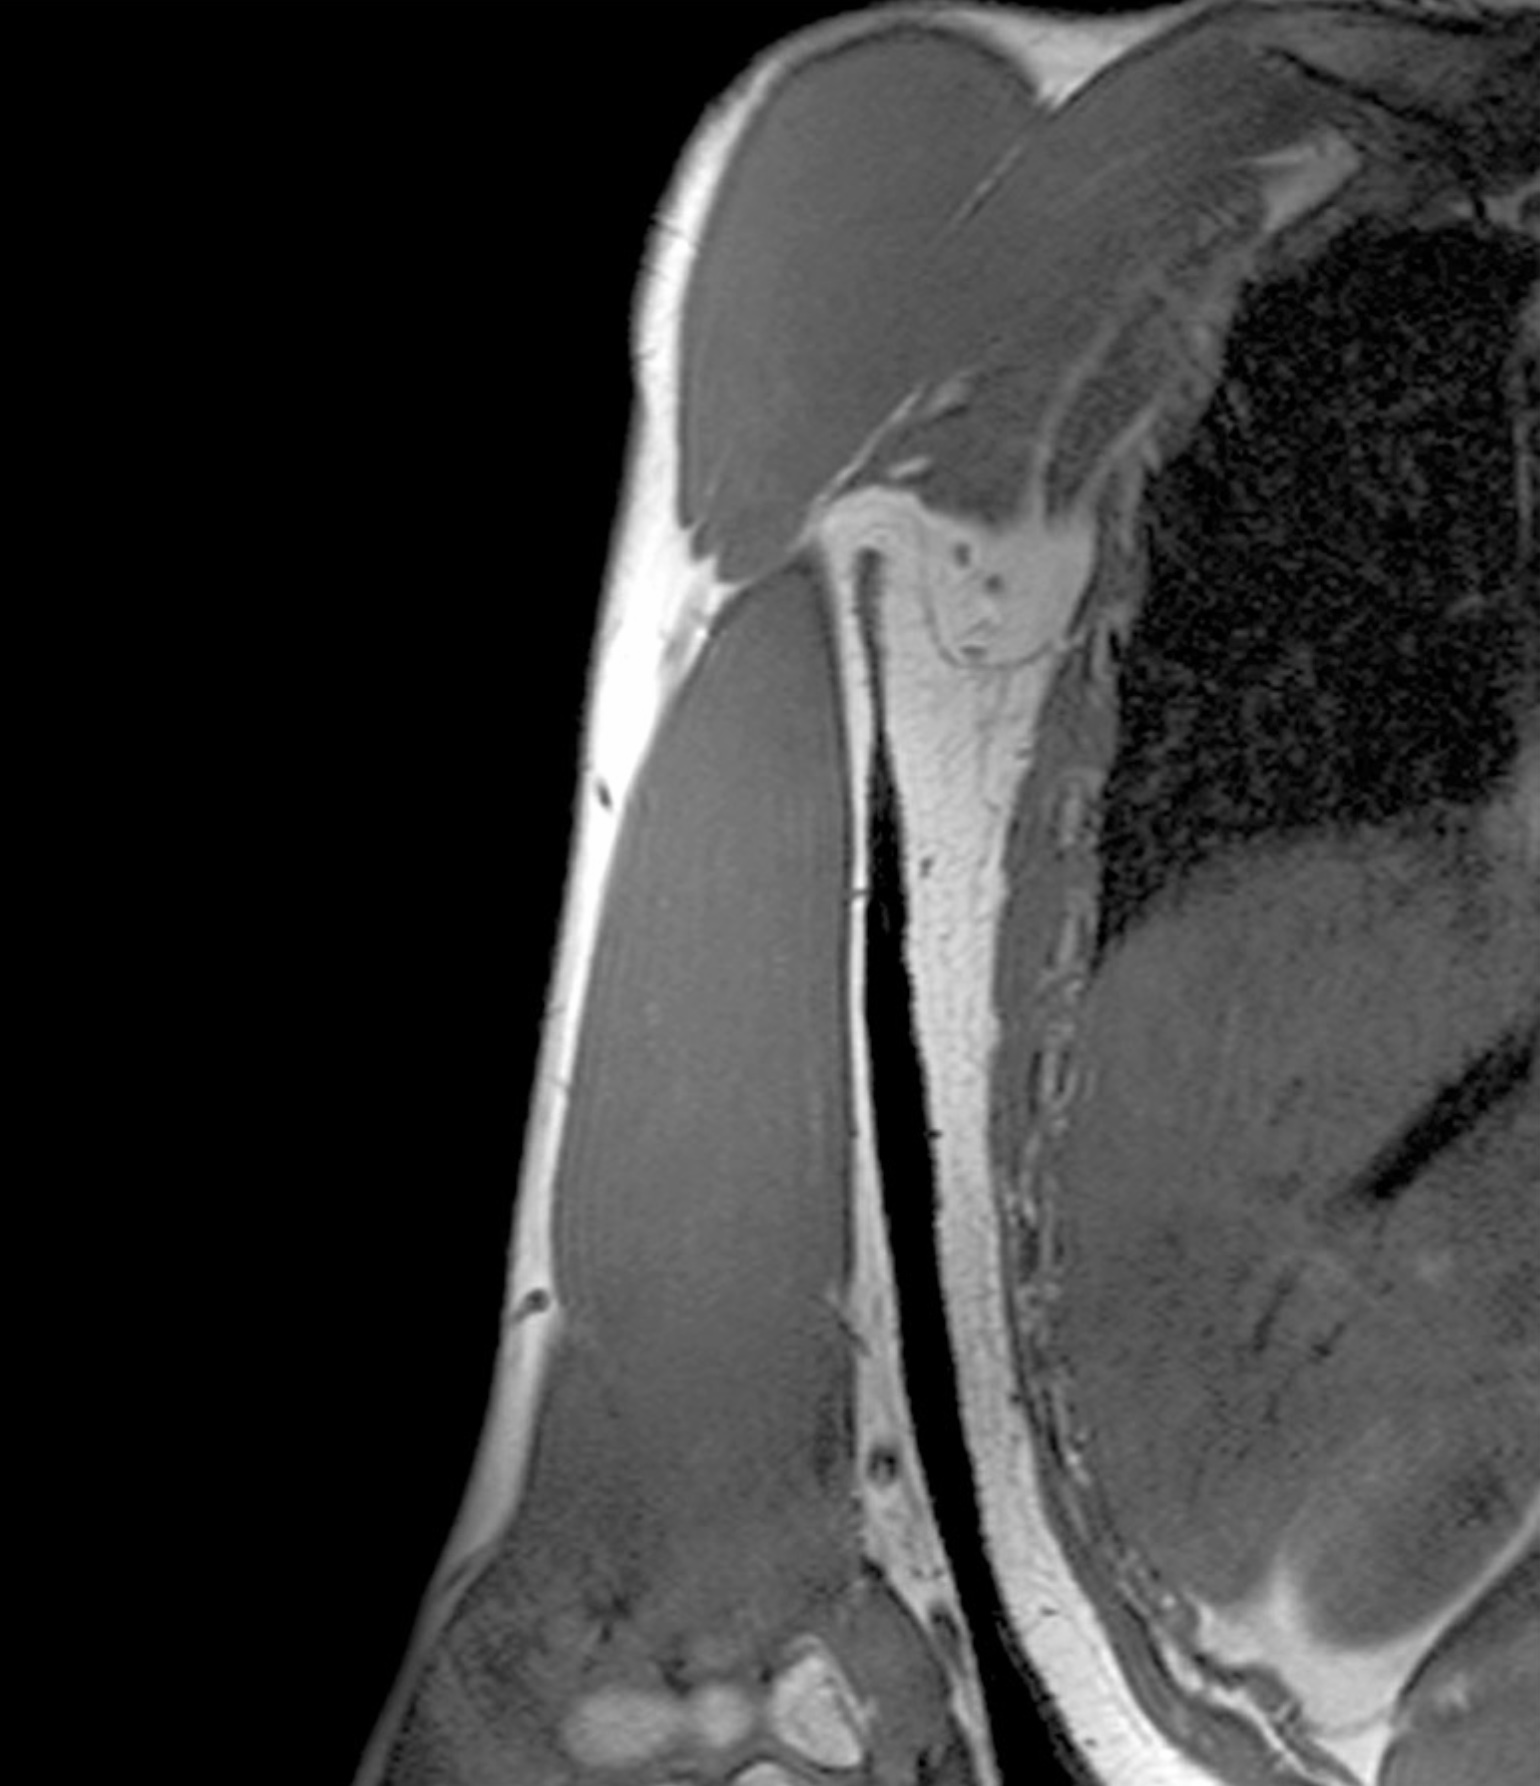

1. A 21 year old man presents to the clinic presenting weakened elbow extension, wrist drop and paresthesia of the posterior arm, lateral arm, dorsal forearm and hand. While you are gathering his history he mentions that it was his 21st birthday last night and had one too many to drink and ended up falling asleep while sitting on his living room table with his arm hanging over the back of the chair. Upon hearing this you diagnose the patient with Saturday night palsy. Discuss the anatomy of the radial nerve with regard to Saturday night palsy. Include structures associated with the pathway of the radial nerve and its branches through the upper limb, muscles, cutaneous branches. What classification of nerve injury would you give this injury and approximately how long will it be until the patient recovers?